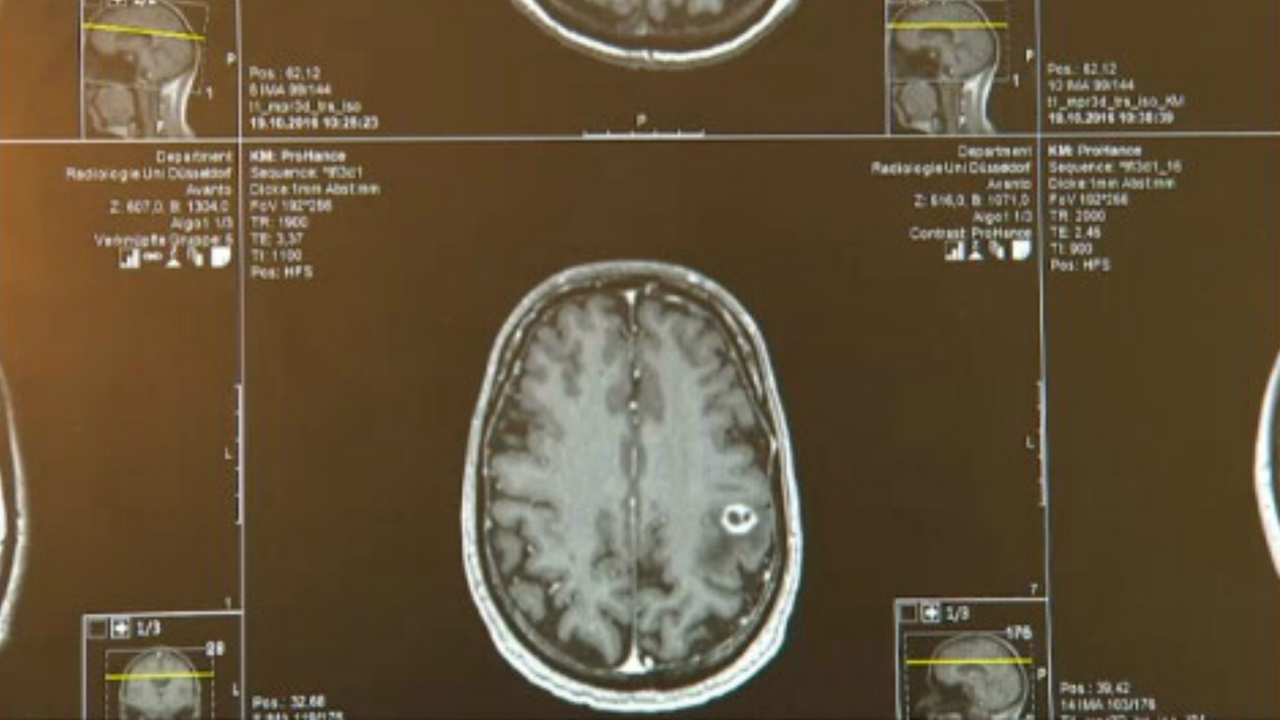

Bei den intrakraniellen im Schädel gelegenen gutartigen Tumoren sind besonders die Tumore des sogenannten Kleinhirnbrückenwinkels Akustikusneurinome und die der Hirnhaut Menigeome zu nennen da sie am häufigsten auftreten. Die Behandlungswege bei Tumorpatienten sind vielfältig oft folgt auf die Operation noch eine Bestrahlung oder Chemotherapie. Diese zielt auf eine möglichst vollständige Entfernung des sichtbaren Tumoranteils unter Erhalt der verschiedenen neurologischen und kognitiven Funktionen des Gehirns ab.

Wenn der Kopf-Hals-Tumor gestreut hat besteht die Operation darin den Tumor und die Halslymphknoten zu entfernen. Die Hirntumor-Operation erfolgt meist in Vollnarkose oder als Wachoperation vgl. Ziel der Operation ist das vollständige Entfernen des Tumors.

Die offene Operation zielt darauf ab den Tumor ganz oder nahezu komplett zu entfernen. Die stereotaktische Biopsie kommt zum Einsatz wenn der Tumor schwer zu erreichen ist. In Vollnarkose gelegentlich auch in örtlicher Betäubung wenn es sich um eine Operation in der Nähe des Sprachzentrums handelt wird der Kopf entsprechend der Lage des Tumors gelagert und in einer.

Hierfür wird der Kopf in einer Drei-Punkt-Kopfklemme fixiert und die Haut gerade oder bogenförmige aufgeschnitten. Mithilfe des zuvor durchgeführten CT oder MRT zeigt dieser genau an wo der Tumor liegt.